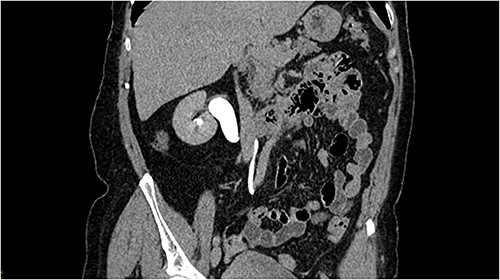

We report a case of a 60-years-old female, who came to our attention for persistent right flank pain and urinary tract infection. The computed tomography (CT) scan revealed right hydronephrosis with dilatation of the upper third of the ureter, up to L4, where it curved posteriorly to the IVC passing to its medial then anterior surface (Fig. 1). The 99mTc mercaptoacetyltriglycine (MAG-3) renal scan showed an obstructed pattern. After obtaining the patient’s consent, a robotic correction of the RCU was planned with the Da Vinci Xi. The patient was placed in lateral position. A pneumoperitoneum was created using a Veress needle, and the four robotic ports, spaced ⁓6 cm apart, were placed in a linear fashion on midclavicular line. Two ports for the assistant were placed at the lateral border of the rectus muscle. After the mobilization of the right colon to expose the retroperitoneal space, the ureter, the gonadic vain, the IVC and the renal pelvis were identified. After the transection of the ureter 3 cm below the ureteropelvic junction, the retrocaval segment was transposed anteriorly to the IVC and an ureteroureterostomy was performed with interrupted 4–0 monofilament sutures. After completion of the posterior layer, a 6F double J stent was insert in a retrograde fashion and the anastomosis was completed (Fig. 2). The operative time was 140 min, of which 90 min of console time. The post-operative stay was regular, the patient was discharged on post-operative day 4. The double J stent was removed after 30 post-operative days. After 1 year of follow-up the patient remains asymptomatic and imaging showed no signs of obstruction.

CT scan reconstruction with the image of the S-shaped ureter behind the IVC.